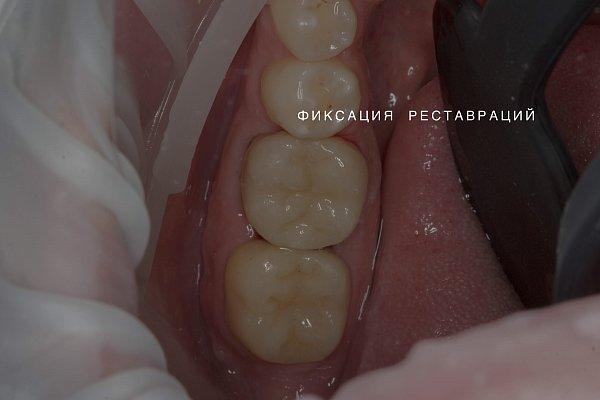

Пациент обратился с жалобами на кариес зубов.

Исходное состояние: Зубы под реставрациями неудовлетворяющими клиническим требованиям

Выполнена реставрация накладками из прессованной керамики.